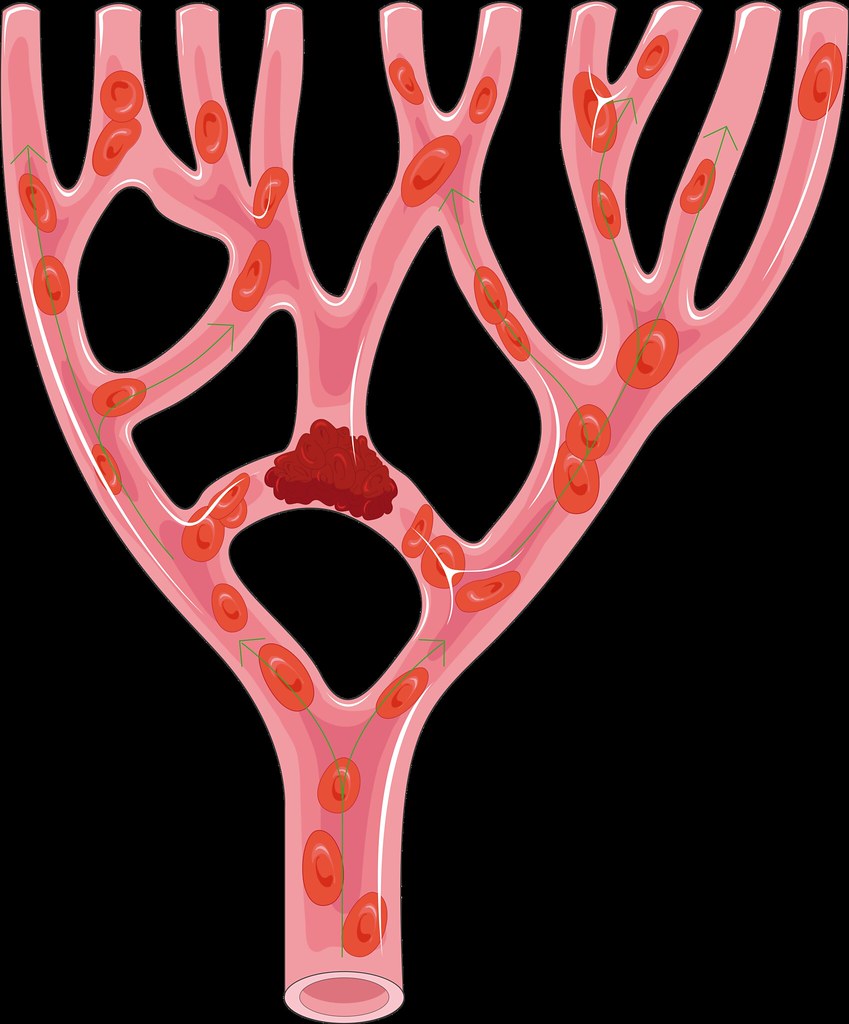

Thrombi in the arteries are usually pale in appearance as they consist mainly of platelets and fibrin that adhere to the arterial wall. Red cells are not trapped in the thrombi as they are swept away by the fast moving flow of blood.

In a large thrombus, alternating layers of platelets and red cells may be seen, which is termed as lines of Zahn.

Venous thrombi are usually friable and appear red in colour due to the numerous red cells that get trapped in the forming thrombi.